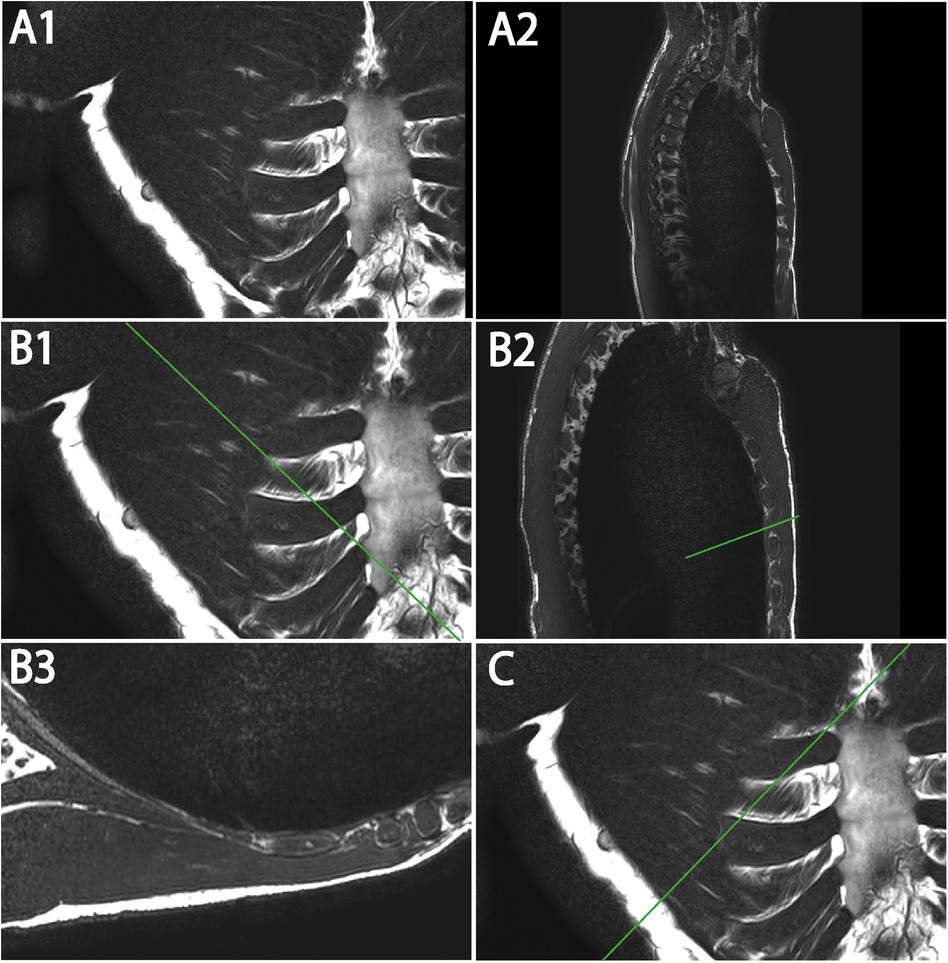

T2W coronal, sagittal, and (para-)axial sequences

The sequences were performed for ventral and dorsal body region scanning (Table 2). Routinely, the coronal images showed the most precise course of ICM in ICS 3. Therefore, ICS 3 was used as a reference for axial imaging of both ICM groups, resulting in two para-axial image series along the direction of cross-sectioned internal and external ICM, respectively (Figure 1). The para-axial image planes were chosen to be perpendicular (tilted 90 °) to the coronal plane at the level of the ICS midpoint and captured the entire origin to insertion of fascicles related to the set midpoint (Figures 3B,C). In addition, sagittal images were routinely prepared (Figure 1A1, B1).

Figure 3

MRI images depict different views of the thorax. Panels A1, B1, and C show axial views with ribs and vertebrae visible. Panels A2 and B2 present sagittal views, highlighting the spine's curvature. Panel B3 shows para-axial view and cross-section of single fascicles.

Figure 3. Representative T2W MRI views (A–C) illustrating coronal (A1) and sagittal (A2) images with marked para-axial plane (line) (B1,B2,C) and exemplary para-axial image (B3). (A1) Original image of coronal T2W. (A2) Original image of sagittal T2W. (B1) Coronal T2W with marked para-axial plane (line) for internal ICM analysis. (B2) Sagittal T2W with marked para-axial plane (line) corresponding to (B) (B3) Original image of para-axial T2W. (C) Coronal T2W with marked para-axial plane (line) for external ICM analysis.